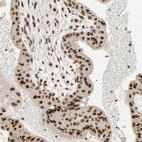

Immunohistochemistry analysis in human testis and skeletal muscle tissues using HPA004198 antibody. Corresponding NCOA6 RNA-seq data are presented for the same tissues.